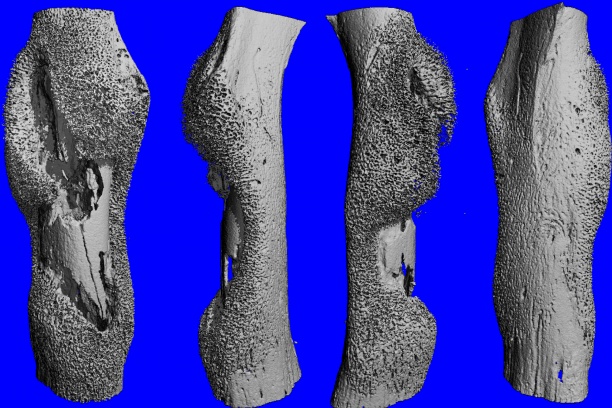

The Cassat Lab studies host-pathogen interactions during invasive bacterial infection, with a special emphasis on understanding how infection and inflammation perturb musculoskeletal cell biology. Osteomyelitis (bone infection) is one of the most common invasive bacterial infections in children, and it also occurs frequently in adults after trauma or surgery. The bacterial factors that promote survival in the bone, as well as the host factors that protect from osteomyelitis, are poorly defined. We have developed a variety of tools to understand how bacteria and inflammation trigger changes in bone biology, including a murine model of Staphylococcus aureus osteomyelitis, high-resolution 3D imaging of bone remodeling, and cell culture models of osteoblast and osteoclast proliferation and function.